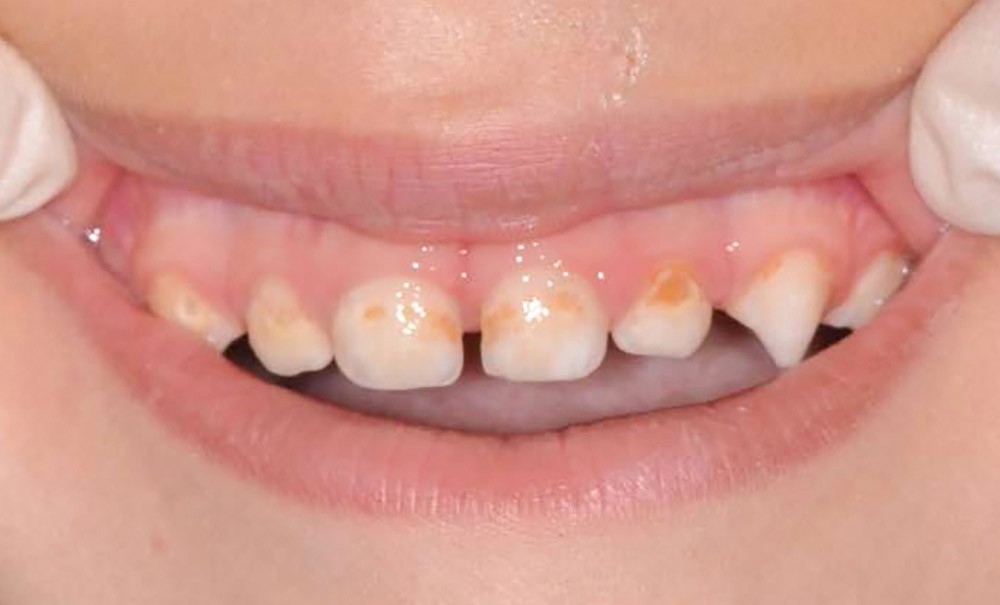

- L’évolution de la maladie carieuse : cette pathologie bactérienne, multifactorielle, se transmet très vite d’une dent à une autre dans la cavité orale de l’enfant. Ainsi, avant l’âge de 6 ans, la carie précoce de l’enfant (CPE) peut atteindre un stade sévère et ne plus permettre à l’enfant de mastiquer sans douleur (fig. 2).

- La perte de chance pour le développement : la CPE non traitée va entraîner l’avulsion précoce de certaines dents, induisant des troubles alimentaires pouvant se répercuter sur le développement général de l’enfant (croissance et développement cognitif), voire de sa vie sociale (absences scolaires répétées, pas de sourire). La CPE a un impact négatif sur la qualité de vie de l’enfant.